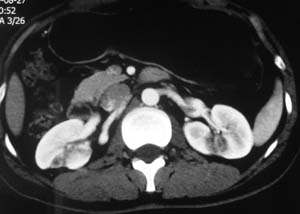

以下是引用子期在2010-3-19 20:47:00的发言:[br]血管畸形的ct增强应该有明显强化,本例并不相符合。本例双肾局部的略低密度影,累及肾盂,局部皮质明显变薄、内陷,增强扫描有轻度的强化,应考虑为炎性病变,患者为年轻男性,累及双肾的感染以结核较常见,可以没有明显的临床症状,尿中有时候也并不能查出什么;肾脓肿常有明显感染中毒症状,本例不符,另外一般的肾盂肾炎或肾小球肾炎通过小便就可确诊,其它还不能排除的是黄色肉芽肿性肾盂肾炎,然而单凭ct一般也很难鉴别。